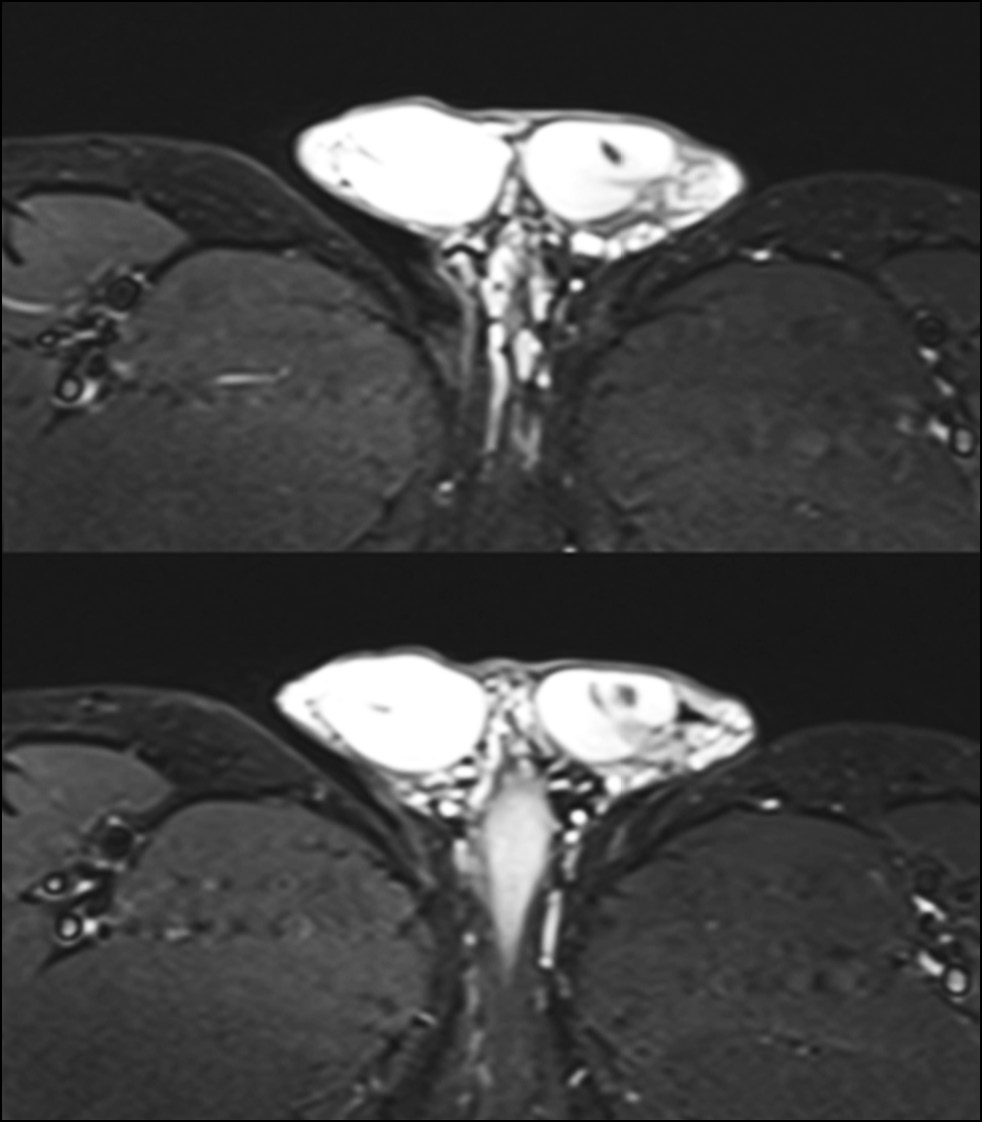

В данной области отмечено усиление контрастности патологического очага, характеризующееся септальным паттерном, особенно в периферической области уровня верхнего полюса. Отёчность была вызвана увеличением придатка яичка, обусловленным левосторонним варикоцеле при наличии тонкого слоя гидроцеле (рис. 6–8).

Рис. 6. Наблюдается усиление контрастности патологического очага в исследуемой области, особенно в верхнем полюсе. В Т1-режиме область даёт изоинтенсивный сигнал по сравнению с остальными тканями яичка. Выделены гиперинтенсивные участки кровоизлияний. После введения контрастного вещества (например, гадолиния) в исследуемой области выявлено отсутствие сосудов с характерным ореолом насыщенности по периферии патологического очага.

Рис. 8. Левостороннее варикоцеле при наличии тонкого слоя гидроцеле.